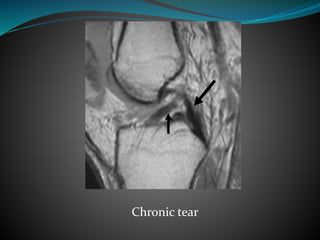

Chronic-

Nonvisualisation of ligament or

Angulation of ligament because of scarring

Shallow orientation not parallel to intercondylar

roof

Chronic tear